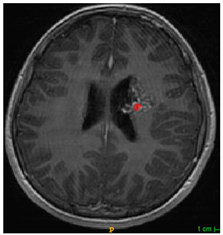

Three cases from the NTUH dataset showing representative results of different models were shown in Table 2, Table 3 and Table 4. The overall dice scores of these networks on the NTUH dataset ranged from 0.33 (DeepMedic) to 0.51 (V-Net). Table 5 shows the detailed performance of each network tested with the NTUH dataset.

Table 4. Predictions with high dice scores.

Ground truthDeconvNetDeepMedic

Applsci 11 09180 i013 Applsci 11 09180 i014 Applsci 11 09180 i015

PSPNetU-NetV-Net

Applsci 11 09180 i016 Applsci 11 09180 i017 Applsci 11 09180 i018